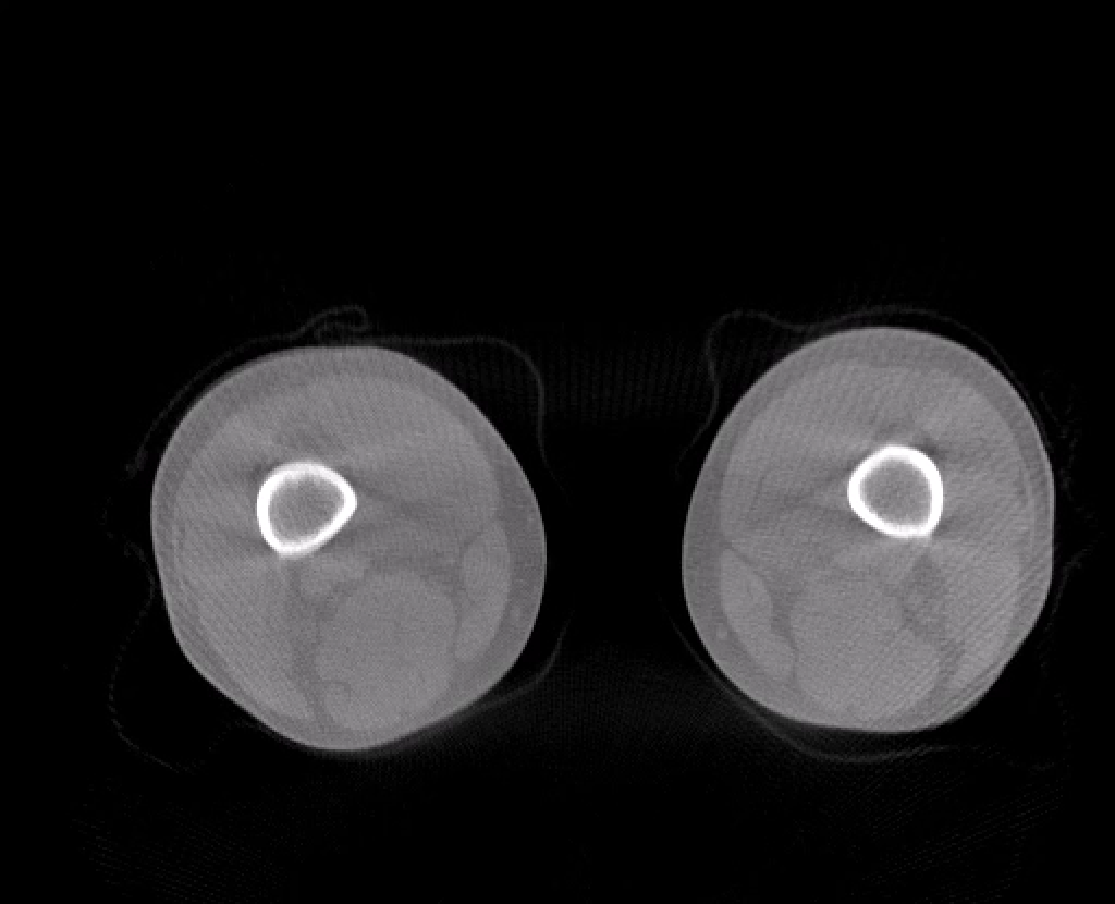

对于安健科技“WR-3D负重位动态三维影像重建系统”技术的问世,主要解决了两大核心问题:1、解决了普放DR漏诊率高的现状,常规DR设备仅有某一角度的二维影像、密度信息极差,而WR-3D能获得更丰富的诊断信息,多角度拍摄三维重建影像,任意角度任意切面以及高敏感的密度信息;2、解决了CT无法获得立位(负重位)的三维影像,WR-3D无论是在断层图像重建、MPR多平面重建、VR体绘制都有着优异的表现,而对于临床诊断尤其是骨科,负重位的影像更具有临床价值。患者在负重位状态下肌肉状态、关节间隙及骨骼力线等都与患者平躺时是明显不同的。因此WR-3D在术前精准规划与术后精准评估方面有其非常重要的临床价值。

(负重位状态下WR-3D断层重建图像)